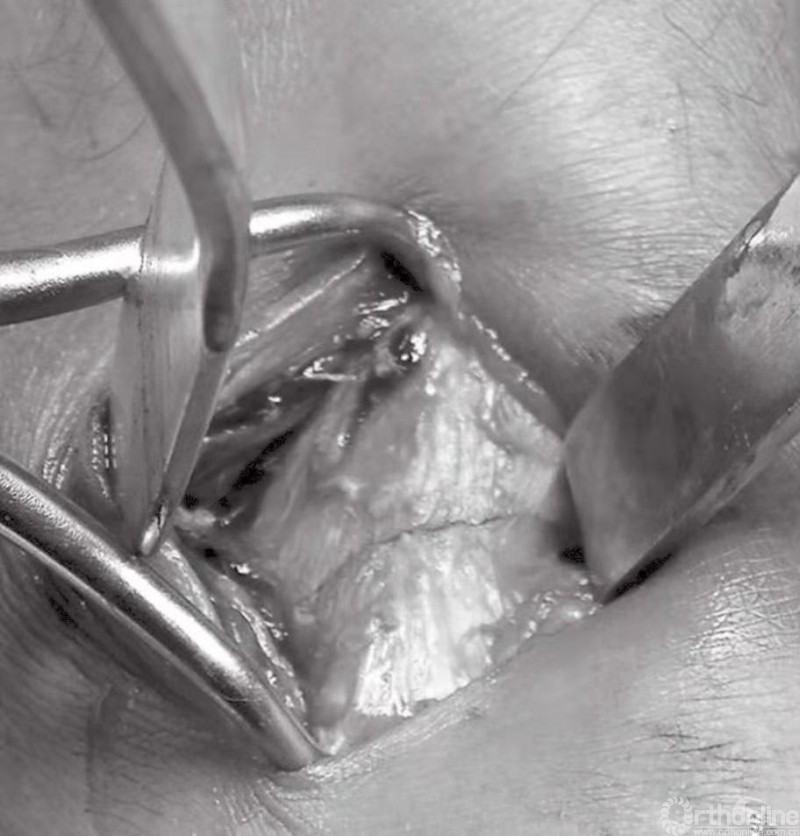

内踝骨折中通常会伴有骨膜撕裂(图11)。这些骨折病例大多数均存在骨膜的介入,这便造成了愈合困难,可能导致骨不连。应将骨膜抬离骨折端,并清理折断表面的血块。将骨折片向远端回缩,以观察关节。在移除关节内所有的游离骨块后,用盐水清洗关节(图12)。

图11 骨膜撕裂及骨折间隙